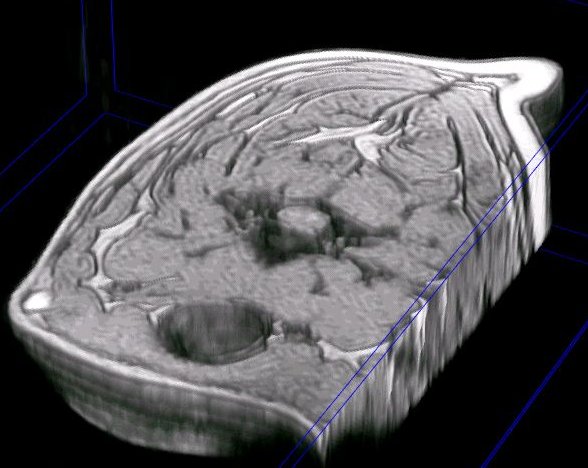

detalle de la columna vertebral cervical en una reconstrucción en 3D del cuello de un perro a partir de imágenes de resonancia magnética (secuencia GE) |